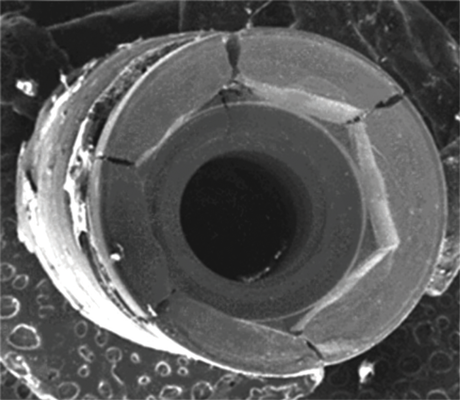

When subjected to loading, cyclic or static, metals may undergo "creep." Creep is a type of metal deformation that occurs at stresses below the yield strength of a metal.22 Regarding dental implants, this may lead to alteration of the platform of the implant through distortion of the connection or by the coronal aspect at the platform becoming "out of round." With an internal type of connection, under continued loading, this may eventually lead to loosening of the abutment on the implant as the intimacy of the fit between the parts decreases or even a fracture of the implant coronally. An external hex connection undergoing creep will demonstrate rounding of the points of the hex. The potential for creep is determined by measuring the percentage of elongation of a material. A higher percentage of elongation indicates a softer metal and higher possible degree of creep. CP-Ti demonstrates a decreasing percentage of elongation from grade 1 to 4 due to a decrease in the softness of the metal. Furthermore, comparisons of CP-Ti grade 4 with Ti-6Al-4V grade 5 reveal a significantly lower potential for creep associated with the alloy.20,23

Implants with internal hex connections are more prone to failure at the connection than those with external hex connections.28 This is related to the thickness of the metal at the thinnest point between the internal surface of the interface and the external surface at the crestal area of the implant. When overloaded, implants with an internal hex connection may present with fractures at the points of the hex.29 These points are where the metal is the thinnest at the crestal portion of the implant and where stress is concentrated during overloading. This is less problematic in wider diameter implants because the metal is thicker in this area of the implant; however, in standard or narrow diameter implants, fracture may result, causing catastrophic failure of the implant (Figure 1). This may also occur in other internal implant connection types, such as trilobe connections, especially when the crestal thickness of the implant is minimal, leading to fracture of the coronal aspect of the implant (Figure 2). Implants with conical connections are not immune to potential fracture in this area, and the thin walls of some standard or narrow diameter models may split even without the isolated stress points observed in internal hex-, trilobe-, and octagon-type connections (Figure 3).30 Sometimes, fractures of implants at the coronal aspect are not clinically visible but, instead, are identified radiographically either after a patient complaint of pain in the area, due to the presence of soft-tissue inflammation, or during a routine examination with no patient complaint (Figure 4).

As discussed, yield strength defines the stress at which metal begins to plastically deform. When presented with off-axis loads over time, an external hex connection on an implant may undergo creep, which leads to rounding of the points because this is where the stress is concentrated. As the points on the external hex deform, they permit greater micromovement of the abutment, which leads to greater stress being placed on the abutment screw and can result in fracture of the screw (Figure 9). When an implant is fabricated from CP-Ti, even grade 4, there is a greater potential for this problem than if it is fabricated from titanium alloy grade 5; however, it occurs less frequently in wider diameter implants.

(3.) An implant with a conical connection demonstrating fracture of the thin walls at the coronal aspect (Radiograph courtesy of Ramsey Amin, DDS).

Figure 3